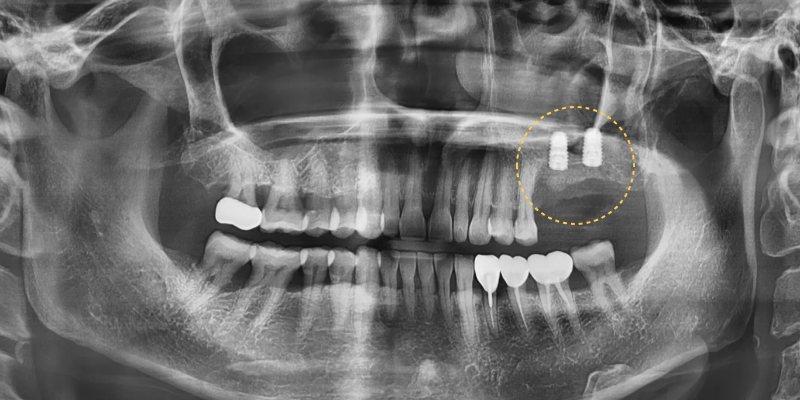

약 3개월간의 회복 기간을 거친 뒤

임플란트 식립과 동시에 추가적인

치조골이식술과 상악동거상술을 병행하여

부족한 뼈를 충분히 보강하였습니다.

위쪽 어금니 부위는 상악동과의 거리 때문에

특히 세심한 접근이 필요했으며

단계적으로 뼈를 회복시키는

방향으로 치료를 진행하였습니다.